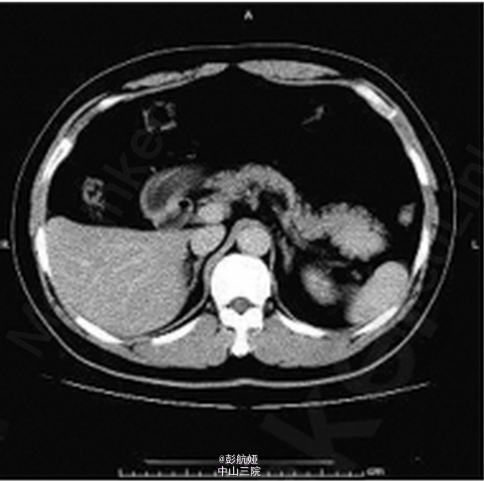

患者 ,男 ,56岁 ,因“体检发现胰尾部占位 2周”入院 ,入院后无明显阳性体征 。 实验室检查 :肿瘤标志物甲胎蛋白6.57ng/mL ,癌胚抗原 3.64ng/mL ,糖类抗原1259.90U/mL ,糖 链抗原 19-912.30 U/mL ,鳞状细胞癌相关抗原0.8ng/mL 。B超检查 :胰腺切面形态失常 ,胰尾部可见一大小3.5 cm × 2.8cm 低回声区 ,边界尚清 ,内部回声不均。胰管不扩张。 彩色多 普勒(CDFI) :门静脉血流充盈 ,上述胰尾部低回声区内未见明显血流信号 ,余部位未见异常血流信号 。 B 超诊断 :胰尾部实质性病灶 。 CT 增强检查 :胰腺尾部可见一肿块影 ,大小约 4.4cm × 3.4 cm × 2.4 cm ,动脉期 、静脉期明显强化(图1、2) ,延迟期强化程度减低 ,且均匀强化(图 3) ,胰尾向前推移 ,肿块位于脾动静脉前下方 ,胰管未见扩张 。脾脏不大 ,密度均匀。 CT 诊断 :胰尾后方肿块、强化 ,多考虑肿瘤性病变 。手术及病理 :行全腹腔镜下胰体尾切除术 。切开胃结肠韧带 ,显露胰腺 ,可见胰腺体尾部约 5 cm × 3 cm 肿块 ,凸向胰体尾背侧生长 ,脾血管未受侵犯。 行胰体尾切除。病理 :送检组织镜下见为基本正常的胰腺组织 ,部分包裹脾脏组织 ,脾小体结构清楚 。符合(胰体尾)副脾 。